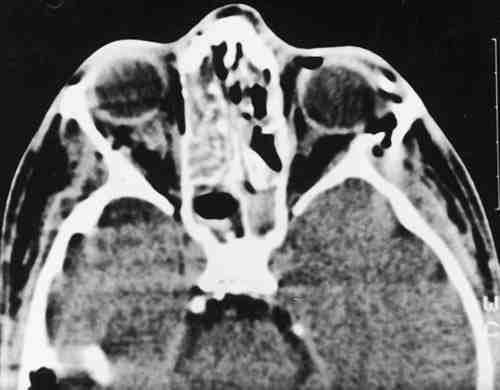

Figura 2

T.A.C. ORBITARIA DONDE SE APRECIAN MÚLTIPLES FRACTURAS FACIALES Y ORBITARIAS, NEUMO-ÓRBITA BILATERAL Y UNA HEMORRAGIA RETROBULBAR IZQUIERDA ALREDEDOR DE LA INSERCIÓN DEL NERVIO ÓPTICO AL GLOBO.